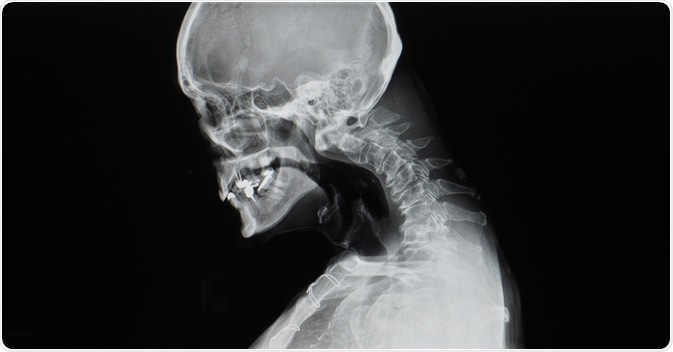

Usually, full-length anteroposterior and lateral radiographs are ordered to allow for proper visualization of the spinal structure. Computerized tomography (CT) of the spine provides supplemental information on eventual bone abnormalities predating or caused by kyphosis. With magnetic resonance imaging (MRI), it is possible to assess the junction of the spinal joints and determine if there is an impingement on the spinal canal of bone structures.